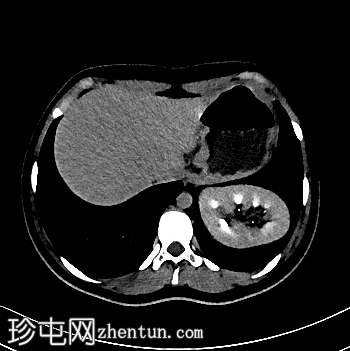

轴位增强扫描

动脉期

左侧Bochdalek疝,大小为8.7 x 7.5 cm,疝颈长3.2 cm。左肾位于胸腔内(Bochdalek疝伴胸内肾),无并发症。左肾旋转不良(过度旋转),肾门朝向后方,肾血管位于后方。肾血管起源正常。肾脏大小为8.6 x 5.8 x 6.1 cm,体积、实质和功能均正常。输尿管膀胱连接处位置正常。未见结石或肾积水。

右肾位置正常,大小正常(头尾径 9.5 cm),肾实质和功能均正常。未见结石或肾积水。